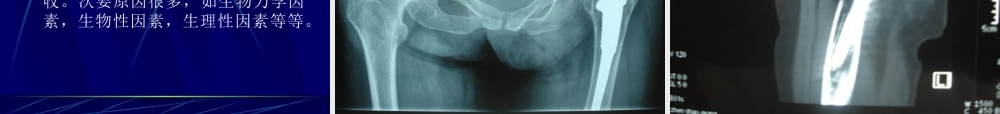

人工髋关节简介现代人工髋关节外科技术,是举世公认的一项人工材料在人体中使用最成功的外科技术。骨溶解与无菌性松动,尚未很好解决,但毕竟它是治疗多种髋关节疾病最普遍而又最有效的方法,不仅可以矫正髋关节畸形,消除疼痛,恢复关节功能,而且大大提高了病人的生活质量。术后容易出现的问题1骨折2感染3脱位4深静脉血栓5双下肢不等长术后容易出现的问题6大腿痛7假体变形和断裂8异位骨化9假体松动骨折发生率最近国外报道假体周围发生骨折的发生率为4.1%-27.8%。骨折原因患者骨质疏松先天性骨质结构异常(四)触四肢骨折的预防1骨质疏松的治疗长期饮用牛奶补充钙质适当的活动接受阳光照射骨折的预防骨折的最直接原因的外伤患者一定要有防摔意识,在日常生活中随时随地注意保护自己。感染发生率是1.6%。感染是人工关节术后的一个灾难性问题,一旦发生,后果是不堪想象的。要控制感染的唯一办法是取出人工关节。(请问各位:取出人工关节我们还能行走吗?)感染的预防1人工关节术后加强体质锻炼。2发生牙龈发炎,及时就诊,不要拖延。3一旦感冒,及时就诊。4皮肤上有伤口,及时治疗。总之,有可能出现炎症的时候,一定要提前控制,防患于未然。人工关节脱位发生率为5%。脱位的预防1关节活动范围过早过大。术后早期过早屈髋超过90°,过早进行髋关节内旋和外旋运动,都有可能出现脱位的危险。2全髋关节术后应避免过分内外旋腿活动,不坐过低凳子,不做下蹲动作。一般都可以预防深静脉血栓发生率为3%。是人工关节术中术后早期死亡的最重要原因。预防的重点是在围手术期,也就是术前和术后二周内。大腿痛发生率为8.3-34%。原因是纤维性固定的假体不稳,假体与骨的弹性模量不相配,假体在体内的刺激作用。目前没有很好的办法,只有对症治疗。假体柄的变形和断裂假体柄的变形和断裂发生率为0.1%。原因:肥胖病人受到外来暴力的病人。异位骨化发生率:国外为5-90%,国内为24.5%。发生原因目前不清楚。异位骨化的外科治疗大多数异位骨化不造成髋关节疼痛和行走困难,可保守治疗。影响到关节活动者,要手术切除。假体松动发生率为10%-15%。主要原因是应力遮挡和骨吸收。次要原因很多,如生物力学因素,生物性因素,生理性因素等等。4、交流与协作医生之间医护之间5、中医特色的发挥——如何突出优势?辨证论治扬长避短给药方法假体松动的预防1减少磨损控制活动量,肥胖病人适当降低体重。2骨质疏松的治疗施行人工关节手术者绝大多数为老龄病人,一方面随...